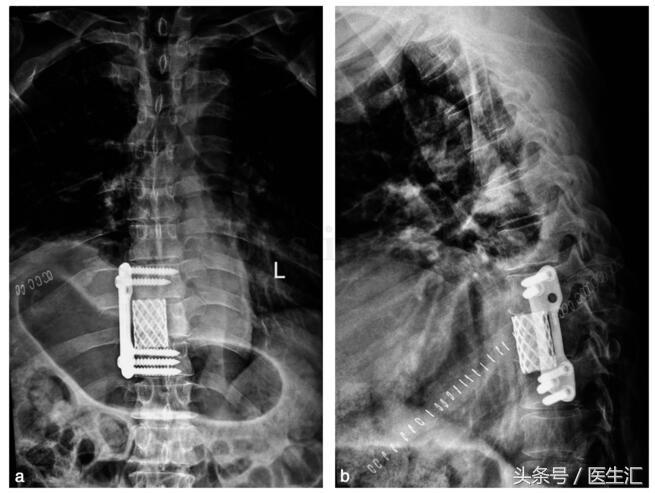

手术治疗:在全麻下行“前路开胸右第7 肋切除,第9 胸椎肿瘤切除椎管减压,Mesh +骨水泥填充植入钛板内固定术”。术后X 线片见图21‐3。

图21‐3 术后X 线片